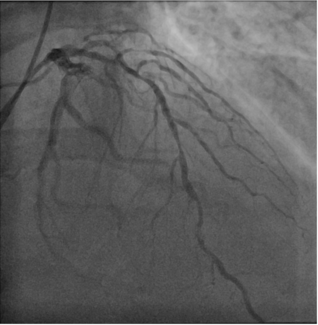

A 60-year-old man was referred for percutaneous coronary intervention of a proximal left circumflex chronic total occlusion with distal filling via epicardial collaterals from the left anterior descending artery. The 30-mm lesion had a...